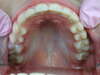

Nos Cas Cliniques orthodontiques 1

Photos après traitement